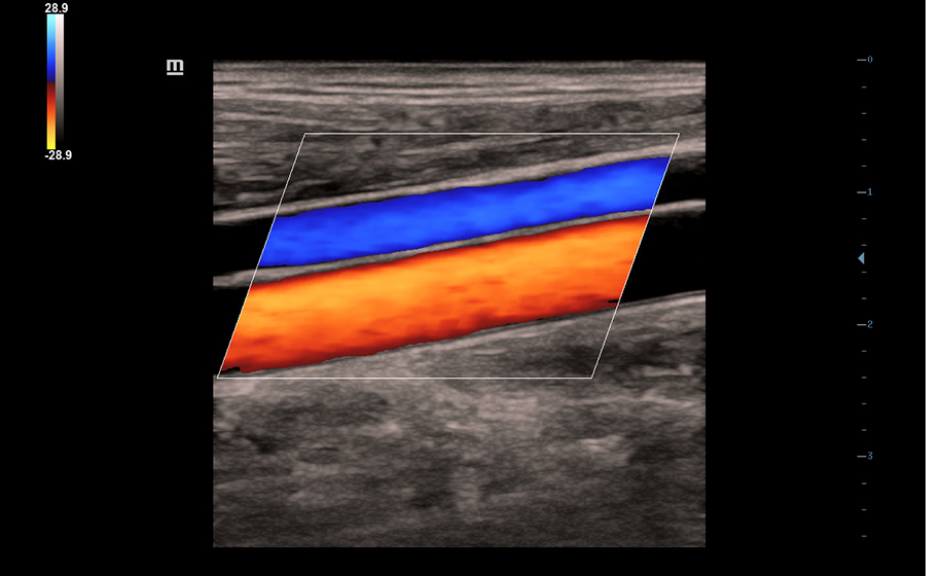

1Ruime keuze aan toepassingsspecifieke onderzoeksvlakken

Vlakpakketten voor verschillende toepassingen: Abdomen, verloskunde/gynaecologie, schildklier, borst, testikel.

Inclusief verschillende (meervoudige) beeldmodi.

Standaard ultrasoundbeelden

3

Vergelijking realtimescan ter referentie.